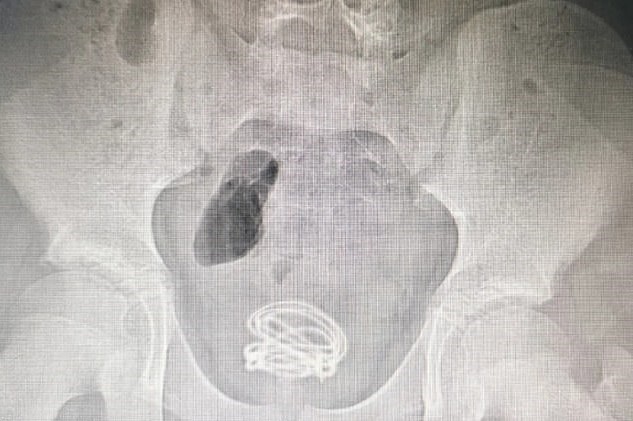

Doctors were shocked to discover the tangled cord inside the boy’s bladder on an X-ray scan.

Medics immediately scheduled Xiao He to undergo the surgery and they pulled out the 2ft. long electrical wire from his urethra.